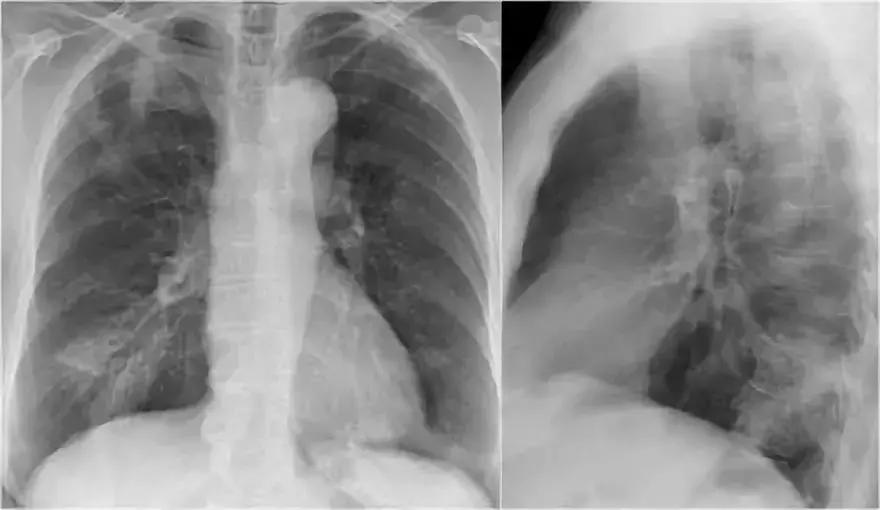

2.病例二

➢ 胸部X线显示,肺右上叶出现密度增加的模糊阴影,肺体积没有缩小

➢ 右肺门在正常的位置

➢ 箭头所示为空气-支气管征

➢ 结合适当的临床诊断,很像大叶或肺段性肺炎

➢ 然而,如果患者出现体重减轻,或症状时间持续较长,可能存在慢性实变的病因。

➢ 诊断结果为,肺炎链球菌引起的急性大叶性肺炎

图4 肺炎链球菌引起的急性大叶性肺炎